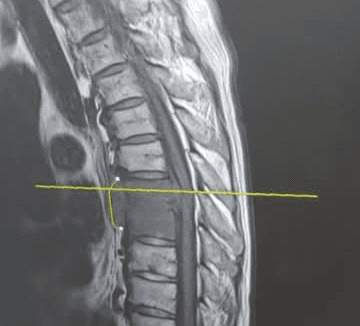

@인공능지: GPT가 한 가족을 구원했군요 (펌 AI 코리아) 🧠 #chatGPT가 구한 #아버지 ✔ 3월 12일 → 아버지, 요로감염으로 쓰러져 응급실 입원 ✔ 한 달 후 → "가슴이 너무 아파 못살겠다"며 다시 #SOS ✔ #정형외과 #종합병원 MRI 결과 → 7번과 8번 척추 사이에 이상 소견 ✔ 대학병원 진료 예약은 '다음 주 월요일' →... $HANARO글로벌생성형AI액티브 $KIWOOM의료AI $TIGER의료기기 $UNICORN생성형AI강소기업액티브 #AI #chatGPT #MRI #SOS #아버지 #인공지능 #정형외과 #종합병원 #퍼온글